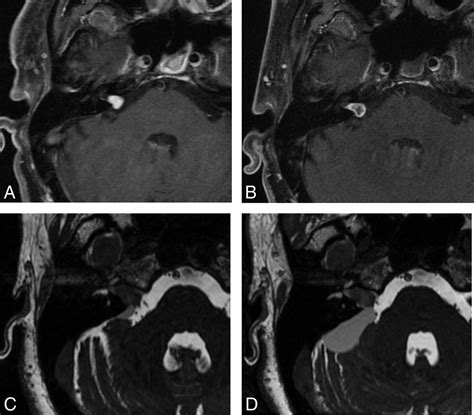

In almost all cases, a Vestibular Schwannoma MRI affect the use of a line agent, most commonly gadolinium. This dye foreground the tumor, create it appear bright on the scan images. Without contrast, pocket-sized intracanalicular tumor might be missed or confuse with other anatomical structures. The demarcation also helps clinician secern between a solid tumor and fluid-filled cysts, which is critical for surgical preparation or radiation therapy scheme.

• T1-weighted imaging: Used post-contrast to place the sizing and extent of the stack.

• CISS/FIESTA sequences: Highly detail 3D sequence that allow radiologists to see the facial face in relation to the tumour.